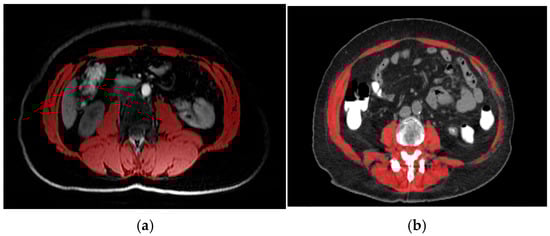

2.2. Assessment of Body Composition and Definition of Low SMI